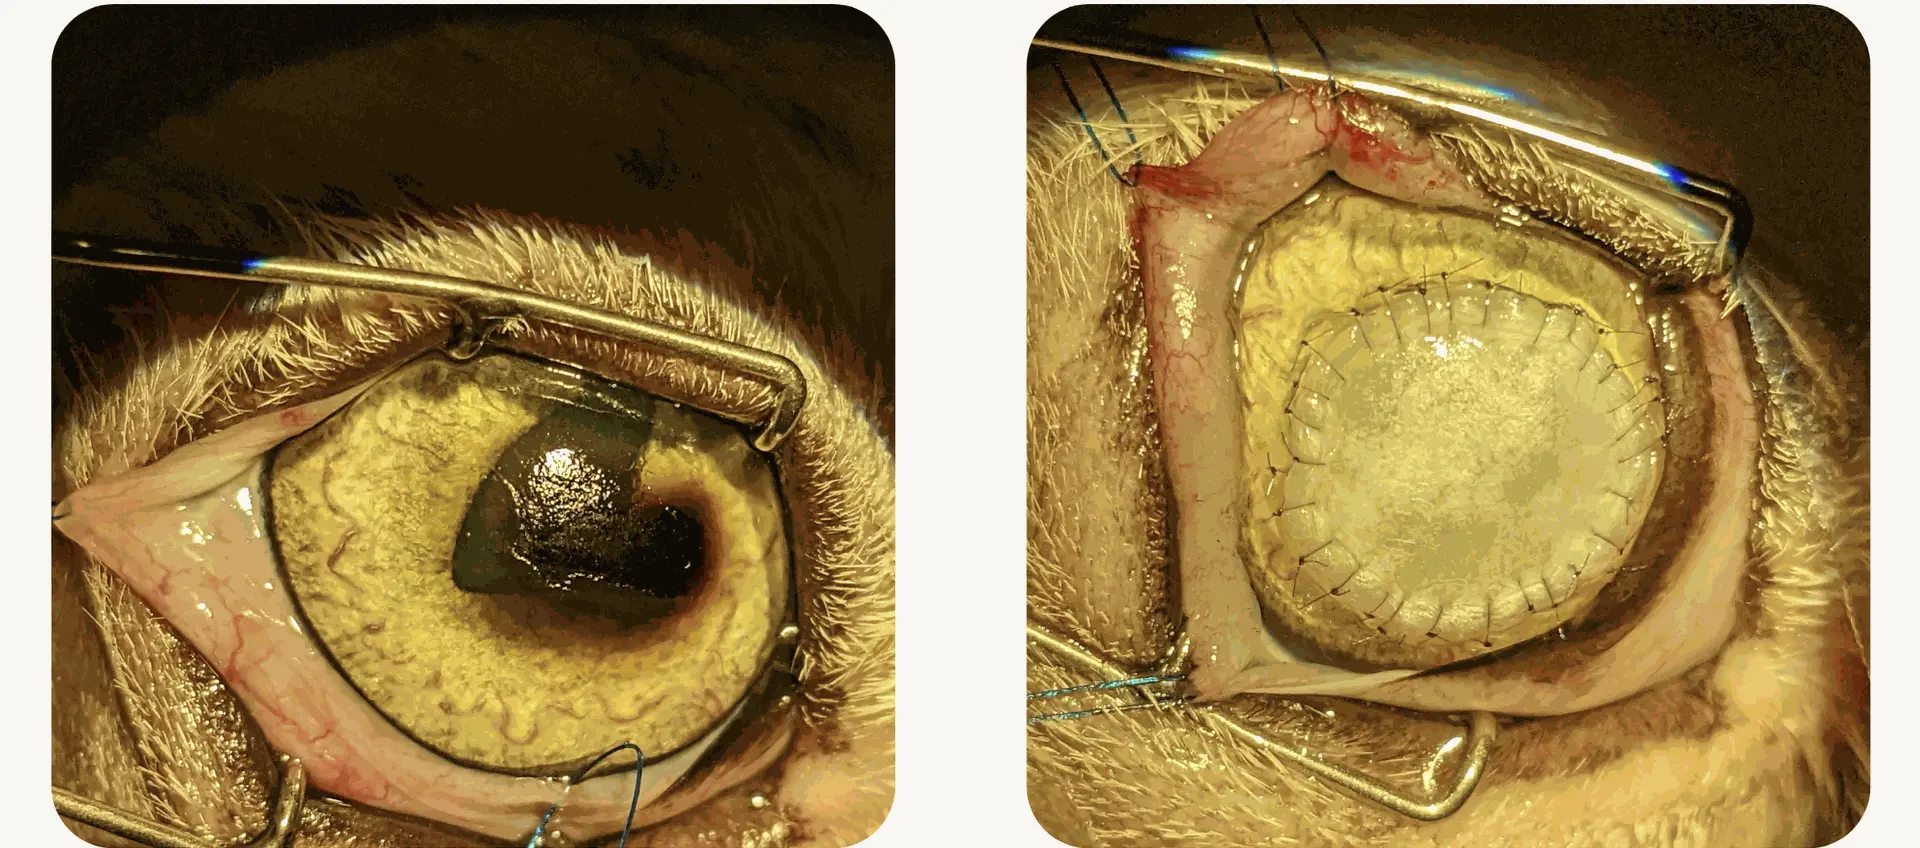

- Suture de cornée

Chirurgie intra-oculaire :